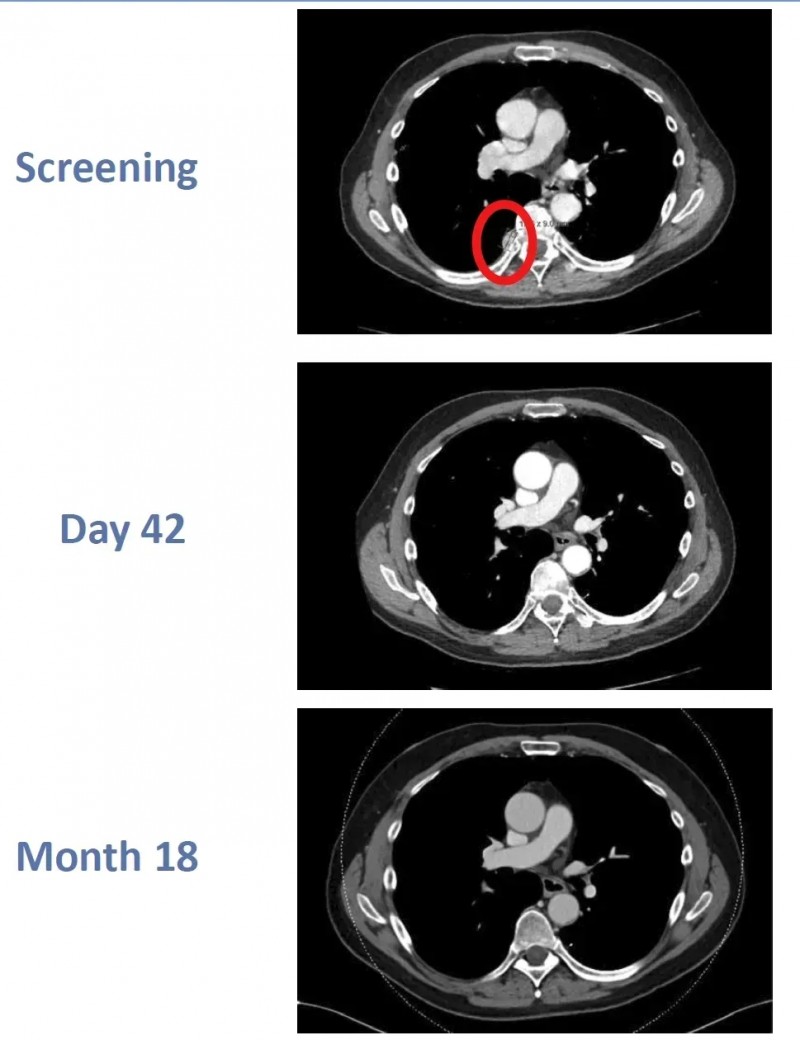

异基因CAR-T首获持久CR:助晚期肾癌患者实现18个月持久无癌

在第37届癌症免疫治疗学会年会(SITC)上,一则突破性案例公布:一名透明细胞肾细胞癌(RCC)患者,经CTX130CAR-T细胞治疗后,奇迹般实现完全缓解(CR),这是异基因CAR-T细胞治疗首次达成如此持久的完全缓解,相关数据同步发表于《癌症免疫治疗杂志》。

该患者是一位64岁男性,确诊透明细胞肾细胞癌后,虽接受过阿替珠单抗与卡博替尼治疗,但病情仍复发且癌细胞转移至肺部、胸膜。因符合入组标准,他加入了CTX130治疗肾癌的1期临床试验(NCT04438083)。

治疗结果显示:该患者接受CTX130后,先达到部分缓解(PR);治疗第3个月,竟奇迹般实现了完全缓解(CR);更令人振奋的是,至治疗第18个月复查时,其完全缓解(CR)状态仍持续。

▼该患者在CTX130治疗前、治疗第42天、治疗第18个月时的影像学对比

▲图源“BMJ”,版权归原作者所有,如无意中侵犯了知识产权,请联系我们删除